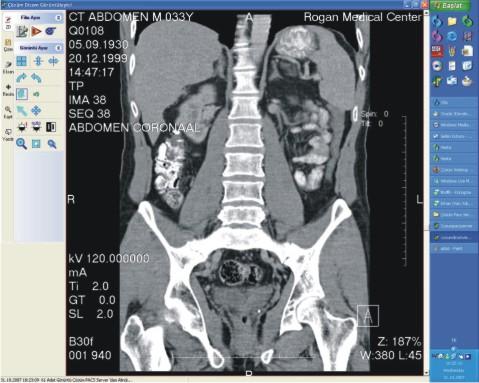

Sayısal görüntüler üzerinde işlem ve ölçüm yapılabiliyor. Görüntüler ve raporların her an, her yerde (tüm iş istasyonları üzerinden sorgulama yapılarak) ulaşılabilir olmasına ve görüntü işleme ve ölçüm (mesafe, açı, uzunluk, yoğunluk) yapılabilmesine olanak sağlıyor.

Radyoloji uzmanlarının tanı süreçlerinin sonuçlanmasında ve doğruluğunda en büyük yardımcı etken Çözüm PACS oluyor [sayısal olarak elde edilen panoromik görüntüler, çözünürlük bozulmadan büyütülüp, belirli bir noktaya odaklanarak, daha detaylı bilgiler elde ediliyor, görüntülerin herhangi bir yerine yazı veya şekil yerleştirmesi ve seçilen görüntünün fare kontrolünde yer değiştirmesi (pan) ve tam ekran incelemesi mümkün oluyor.] İncelenen görüntüler istenildiğinde DICOM yazıcılara gönderilerek film olarak basılabiliyor.

Çözüm PACS, tanı ve teşhislerde daha doğru sonuçlar elde edilmesini sağlayarak sonuçları yorumlama ve raporlama süresini hızlandırıyor. Görüntülerin karşılaştırılması ve radyolojik bulguların geriye dönük değerlendirilmesi, karşılaştırmalı raporların incelenmesi, hekimin hastalığın gelişim sürecini daha iyi kavramasını ve doğru teşhisi daha hızlı bir şekilde koyabilmesini sağlıyor.

Sayısal görüntülerin ayrı ekranlarda karşılaştırılmasını (yan yana iki çalışma şeklinde, yatay ya da dikey olarak bölünmüş, ters çevirilmiş vb.) sağlayarak, zaman içinde oluşan değişikliklerin değerlendirilmesine, (önceki verilerle karşılaştırma) konsültasyon olanaklarının artırılmasına yardımcı oluyor.